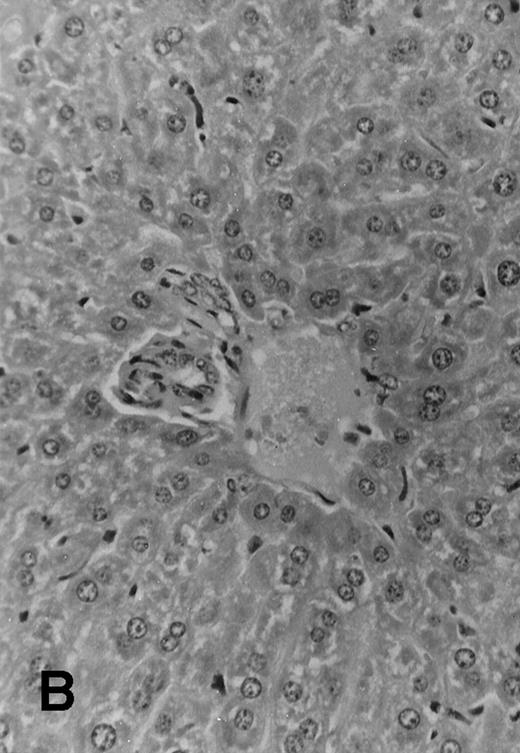

Five of 6 (83%) of (SJL × C57.BL6) F1 mice that received 1 × 106 TCD parental SJL BM cells survived to day +51 posttransplant. These mice appeared healthy and active, with a median weight of 35 ± 1.4 g. All 7 F1 mice that received TCD SJL BM and 30 × 106 irradiated (7.5 Gy) SJL splenocytes survived without evident clinical signs of GVHD. These mice appeared healthy and had a median weight of 35 ± 1.8 g. Seven of 8 (87.5%) F1 mice, which received a combination of SJL TCD BM and 30 × 106 nonirradiated SJL splenocytes, survived to day +51. However, these mice were wasted with a median weight of 24.4 ± 3.4 g and had patchy alopecia and diarrhea (Table 2). Necropsy of all surviving animals at day +51 showed lymphoid hypoplasia among recipients of nonirradiated allogeneic splenocytes. These animals had spleens with mean weights of 30 ± 20 mg compared with normal spleen weights among recipients of TCD BM alone (160 ± 30 mg, P < .0001) or TCD BM plus irradiated allogeneic splenocytes (150 ± 30 mg,P < .0001). Histology examination of samples of skin, liver, and intestine from transplanted mice showed variable degrees of lymphocytic infiltration of the liver, epithelial thickening, and autolysis and sloughing of intestinal epithelium. Evidence for acute GVHD was minimal among recipients of TCD BM alone (Fig 4A) or irradiated allogeneic lymphocytes (Fig 4B). Histologic examination of the liver from recipients of nonirradiated allogeneic splenocytes showed acute and chronic inflammation of the portal tract (Fig 4C) and focal hepatic parenchymal injury. The hepatic GVHD score (on a scale of 0 to 3) and overall GVHD score (on a scale of 0 to 6) for each animal was calculated according to the Materials and Methods section. Recipients of nonirradiated splenocytes had higher GVHD scores than the group that received irradiated splenocytes and the group that received TCD BM alone (Table 2).

Histology sections of liver from recipients of MHC mismatched TCD BM and allogeneic splenocytes. Sections of liver from (C57.BL6 × SJL) F1 mice that were transplanted on day 0 with 1 × 106 SJL TCD BM cells alone (A) or TCD BM in combination with 30 × 106 irradiated (7.5 Gy) splenocytes from SJL donors (B) or with 30 × 106 nonirradiated splenocytes (C). Mice were euthanized at day +51 and samples of liver tissue were fixed in 10% formalin, embedded in paraffin, and sections were stained with hematoxylin and eosin. Original magnification is ×165 in all 3 photomicrographs.